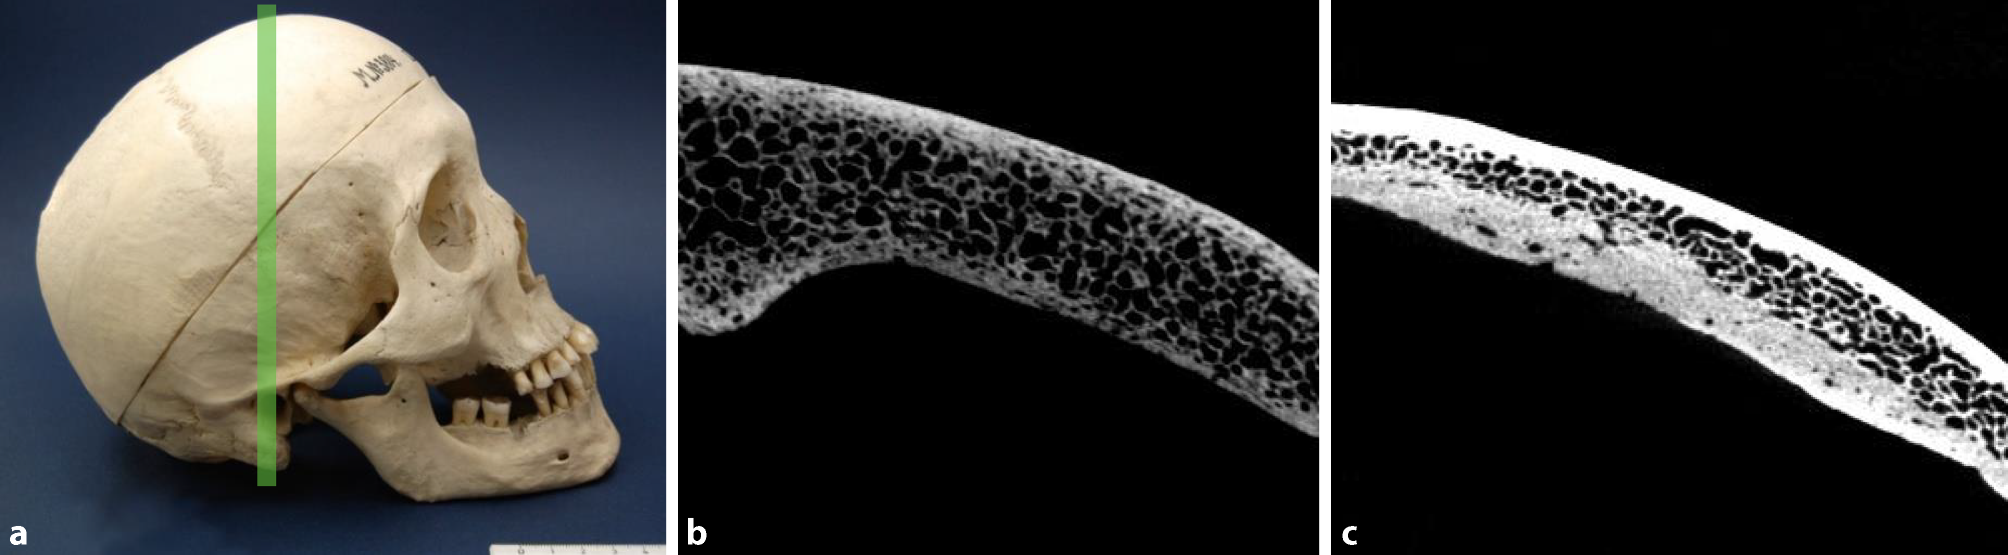

Fig. 1

Cortical porosity. Skull of a 52-year-old man presenting with syphilis compared to a 66-year-old male skull without syphilitic signs used as a control. a Photograph of the syphilitic skull. The green line specifies the plane of the scan. b Cross-section of the affected frontal bone obtained by µ‑CT showing porous structure of both tables. c Skull bone of a 66-year-old man used as a control. Both tables are intact and clearly distinguished from the intervening diploe

The analysis and the following comparison showed that in all affected individuals suffering from syphilis, increased porosity occurred (Table 2). For example, in the skull of a 52-year-old male presented in Fig. 1, this feature was pronounced in both the external and internal tables of the frontal bone. Fig. 1c depicts a skull of 66-year-old male lacking any infectious lesions used as a control.